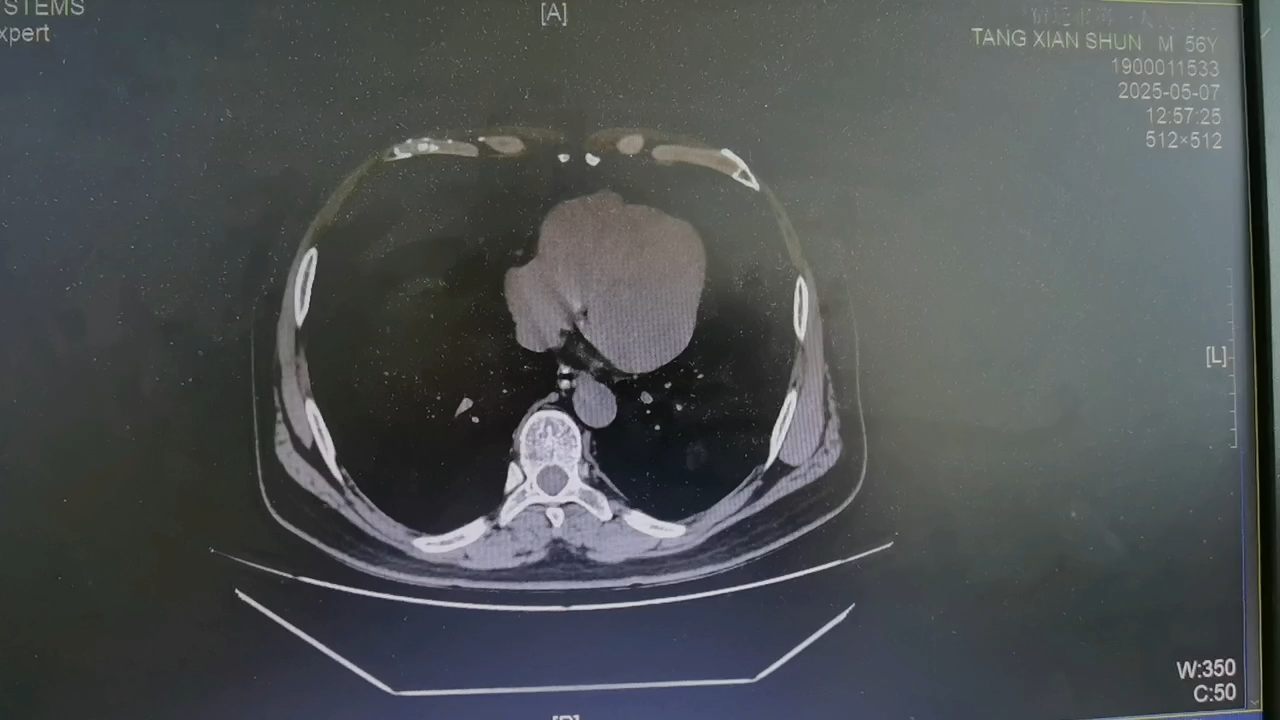

【检查】:CT检查提示右侧腰部切口疝复发。

患者采用健侧卧位,原计划做TEP,术中发现原先手术IPOM植入的补片和腹膜黏连紧密,腹膜前间隙难以分离进入,改行TAPP,下面是术中腹腔镜的情况。术中发现原先的补片已前腹壁以为,补片局部向外突出,形成了疝,腰部补片没有覆盖的区域也形成了疝。